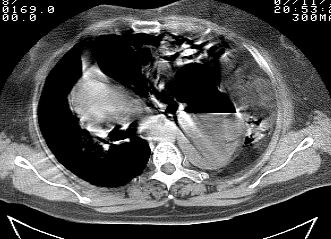

标题: CT10753:女, 64岁 隔疝 [打印本页]

标题: CT10753:女, 64岁 隔疝

女, 64岁 三十年前胸部外伤史, 间断胸闷,

典型左侧膈疝,疝出物为胃和大网膜,纵隔右移

稀钡剂造影就更好了

典型左侧膈疝,如此严重少见。